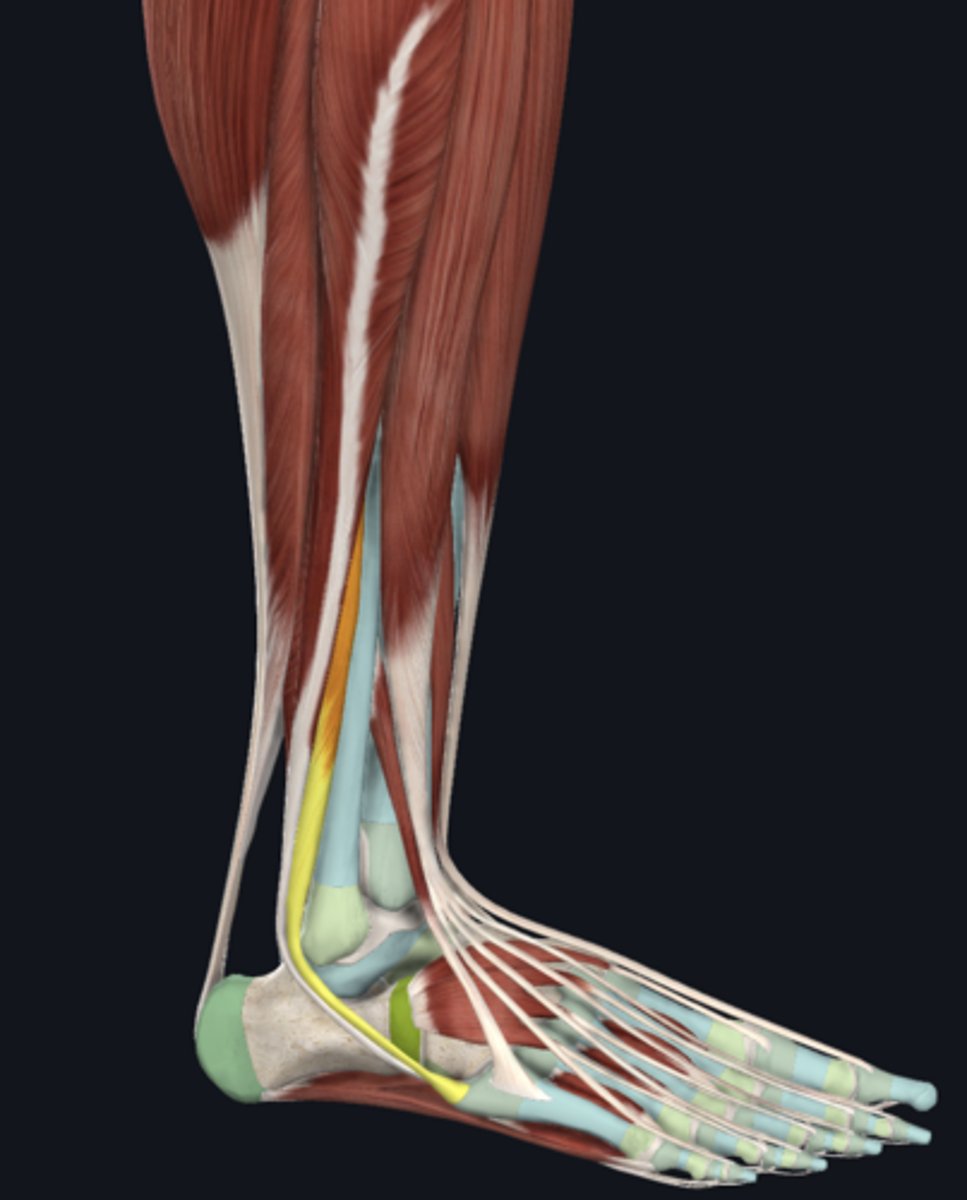

Flexor digitorum longus

tendon in tarsal tunnel

Flexor hallucis longus

tendon in tarsal tunnel

Tibialis posterior

tendon in tarsal tunnel

Tibial nerve (in tarsal tunnel)

nerve

Posterior tibial artery (in tarsal tunnel)

artery

Posterior tibial vein (in tarsal tunnel)

vein

Superior extensor retinaculum

Inferior extensor retinaculum